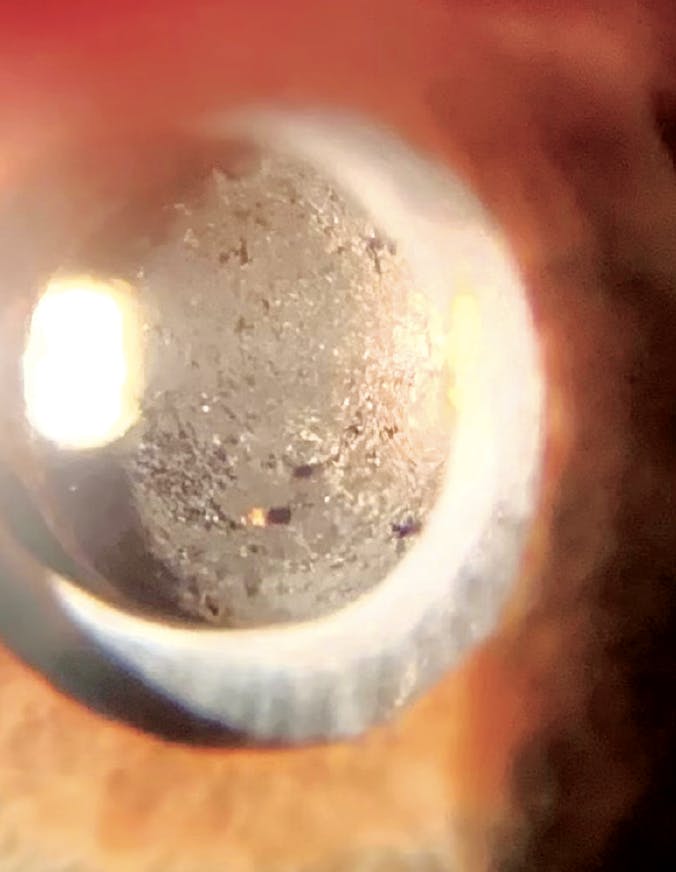

A new patient presented to my clinic complaining of decreased vision in his right eye (Figure). His VA was 20/50 OD and he reported an ocular history of cataract surgery in each eye and uneventful Nd:YAG laser capsulotomy in each eye. The patient requested “another laser to polish up my implants;” however, there was a little more to the story this time.

IOL opacification occurs when deposits of calcium accumulate on the surface of an IOL and/or within the lens itself, not to be confused with posterior capsular opacification, in which cloudy scar tissue forms behind the lens. Calcium bicarbonate (CaHPO4) and hydroxyapatite (Ca5(PO4)3(OH)) are thought to be the most common complexes that create opacification.1,2 Protein precipitates may also be involved, but to a lesser degree.2 Vision may be affected, depending on the amount and location of the deposits.

Because these deposits reside not only on, but also within the IOL itself, laser treatment has little effect and may even worsen symptoms by further disrupting the IOL.1 IOL exchange is the preferred method of managing IOL opacification.1-3